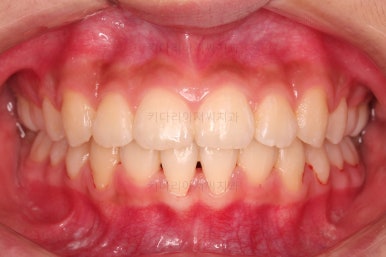

부산치아교정치과 키다리아저씨치과에서 마무리한 입안의 모습입니다.

가지런하게 잘 정렬이 되었고요.

윗니만 발치한 편악발치교정이지만 틈새 없이 공간이 닫혔으며 교합도 잘 맞습니다.

위아랫니가 가지런하게 보기 좋게 배열이 되었고요.

아랫니까지 윗니를 넣음으로써 튀어나와 보이던 앞니의 느낌이 좋아졌습니다.

물론 작은 아래턱에 맞춰 윗니를 뒤로 집어넣어야 해서 자칫 지나치게 들어간 입이 될까 염려되는 조심스러운 케이스였지만, 편악발치를 통해 최소한으로 입을 넣으면서 굉장히 조화롭게 잘 마무리 했습니다.

웃을 때 보이는 앞니의 느낌과 위치가 참 좋아졌네요.